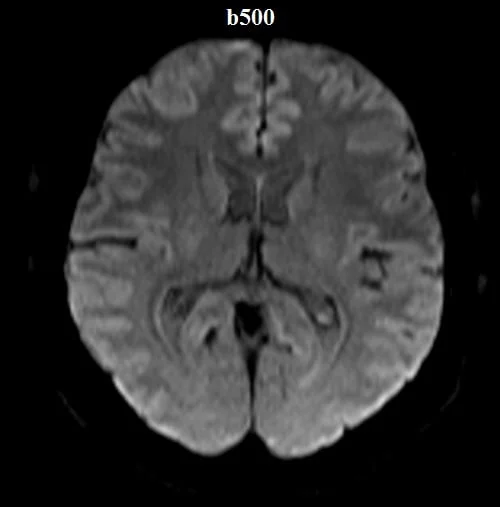

Diffusion-weighted (DWI) axial sequences with b-factors of b0, b500, and b1000 are used in brain imaging.

b-value 500

The magnitude of water signal attenuation on diffusion-weighted images depends on two factors: the translational movement of water molecules, and the amount of diffusion weighting. The latter varies based on the strength, duration, and separation time of the gradient pulses. The sensitivity to water diffusion is defined by the gradient factor “b” (sec/mm²). The higher the “b” values, the better the sensitivity of diffusion-weighted imaging (usually three to four “b” values are used in diffusion-weighted sequences: b50, b500, b1000, and b1400).

The contrast between the b0 and b1000 images helps identify areas of altered tissue microstructure. Regions with higher signal intensity on the b1000 image compared to the b0 image can indicate restricted diffusion areas, potentially signifying pathology. This information is particularly valuable in fields like neurology and oncology, where DWI images assist in identifying conditions such as tumors, strokes, and hemorrhages based on tissue diffusion properties.